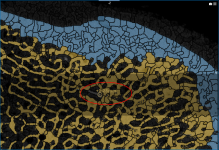

In some cases, an automated segmentation may result in voxels corresponding to trabecular bone erroneously labeled as cortical bone, as circled below, or vice versa.

Automated segmentation result